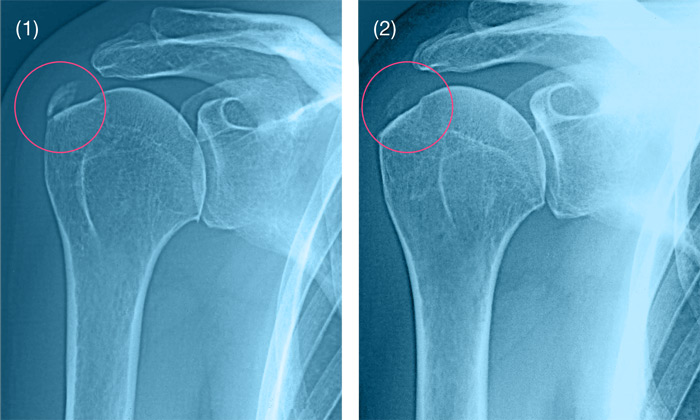

Медицинские снимки: рентген коленного сустава при остеопорозе